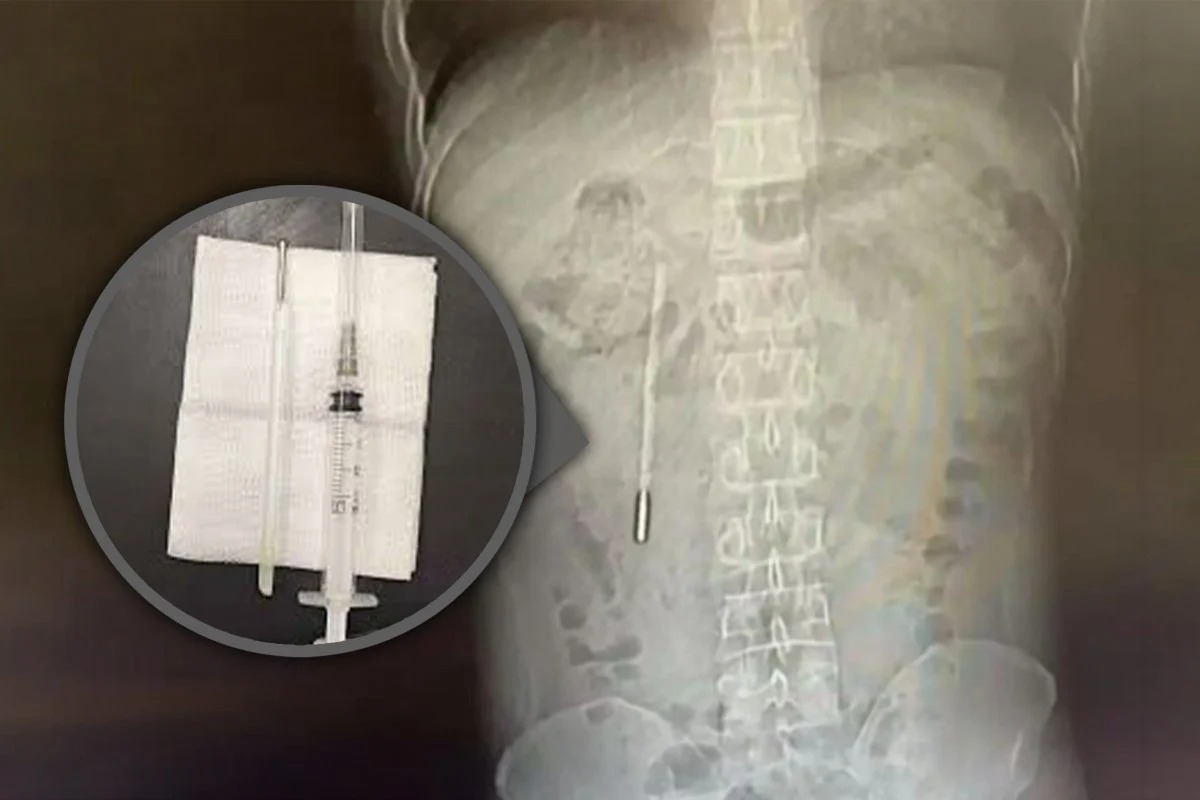

Chiếc nhiệt kế đã nằm trong bụng người đàn ông suốt 20 năm sau khi nuốt phải từ năm 12 tuổi - Ảnh: SCMP

Kết quả chụp X-quang phát hiện một dị vật trong tá tràng, được các bác sĩ xác định là chiếc nhiệt kế thủy ngân. Do đầu nhọn của nhiệt kế cắm trực tiếp vào thành ruột, bệnh nhân đối mặt nguy cơ cao bị thủng ruột và xuất huyết nội nghiêm trọng.

Các bác sĩ phẫu thuật lấy dị vật ra ngoài chỉ trong 20 phút. Đây là ca can thiệp đòi hỏi độ chính xác cao do nhiệt kế lưu lại trong cơ thể quá lâu và nằm gần ống mật, tiềm ẩn nguy cơ tổn thương thành ruột trong quá trình thao tác.

Chiếc nhiệt kế sau khi được lấy ra vẫn còn nguyên vẹn, song các vạch đo nhiệt độ đã phai mờ theo thời gian.